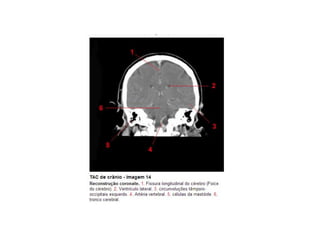

Anatomia E Protocolo Tomografia Computadorizada de Crânio PPT